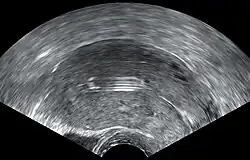

- Ovarian cysts: Enlarged follicles (ovarian cysts) have been diagnosed in about 12% of the subjects using a hormonal IUD in studies that use ultrasound to look for cysts, even if asymptomatic. In studies that only evaluate symptomatic cysts, only 4.5% of women complain of any ovarian cysts over 5 or more years of use, and only 0.3% require IUD removal for ovarian cysts.[60] Thus, any issues with ovarian cysts are not of a clinically relevant nature. Most of these follicles are asymptomatic, although some may be accompanied by pelvic pain or dyspareunia. In most cases the enlarged follicles disappear spontaneously after two to three months. Surgical intervention is not usually required.[61]